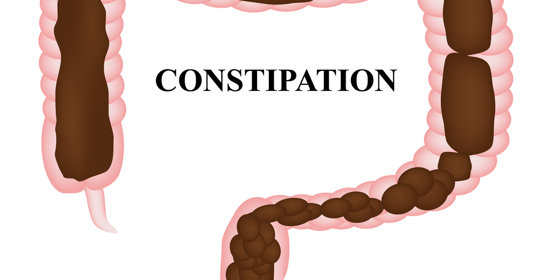

嬰兒拉稀:處理措施與護理建議

嬰兒拉稀:症狀與處理方法